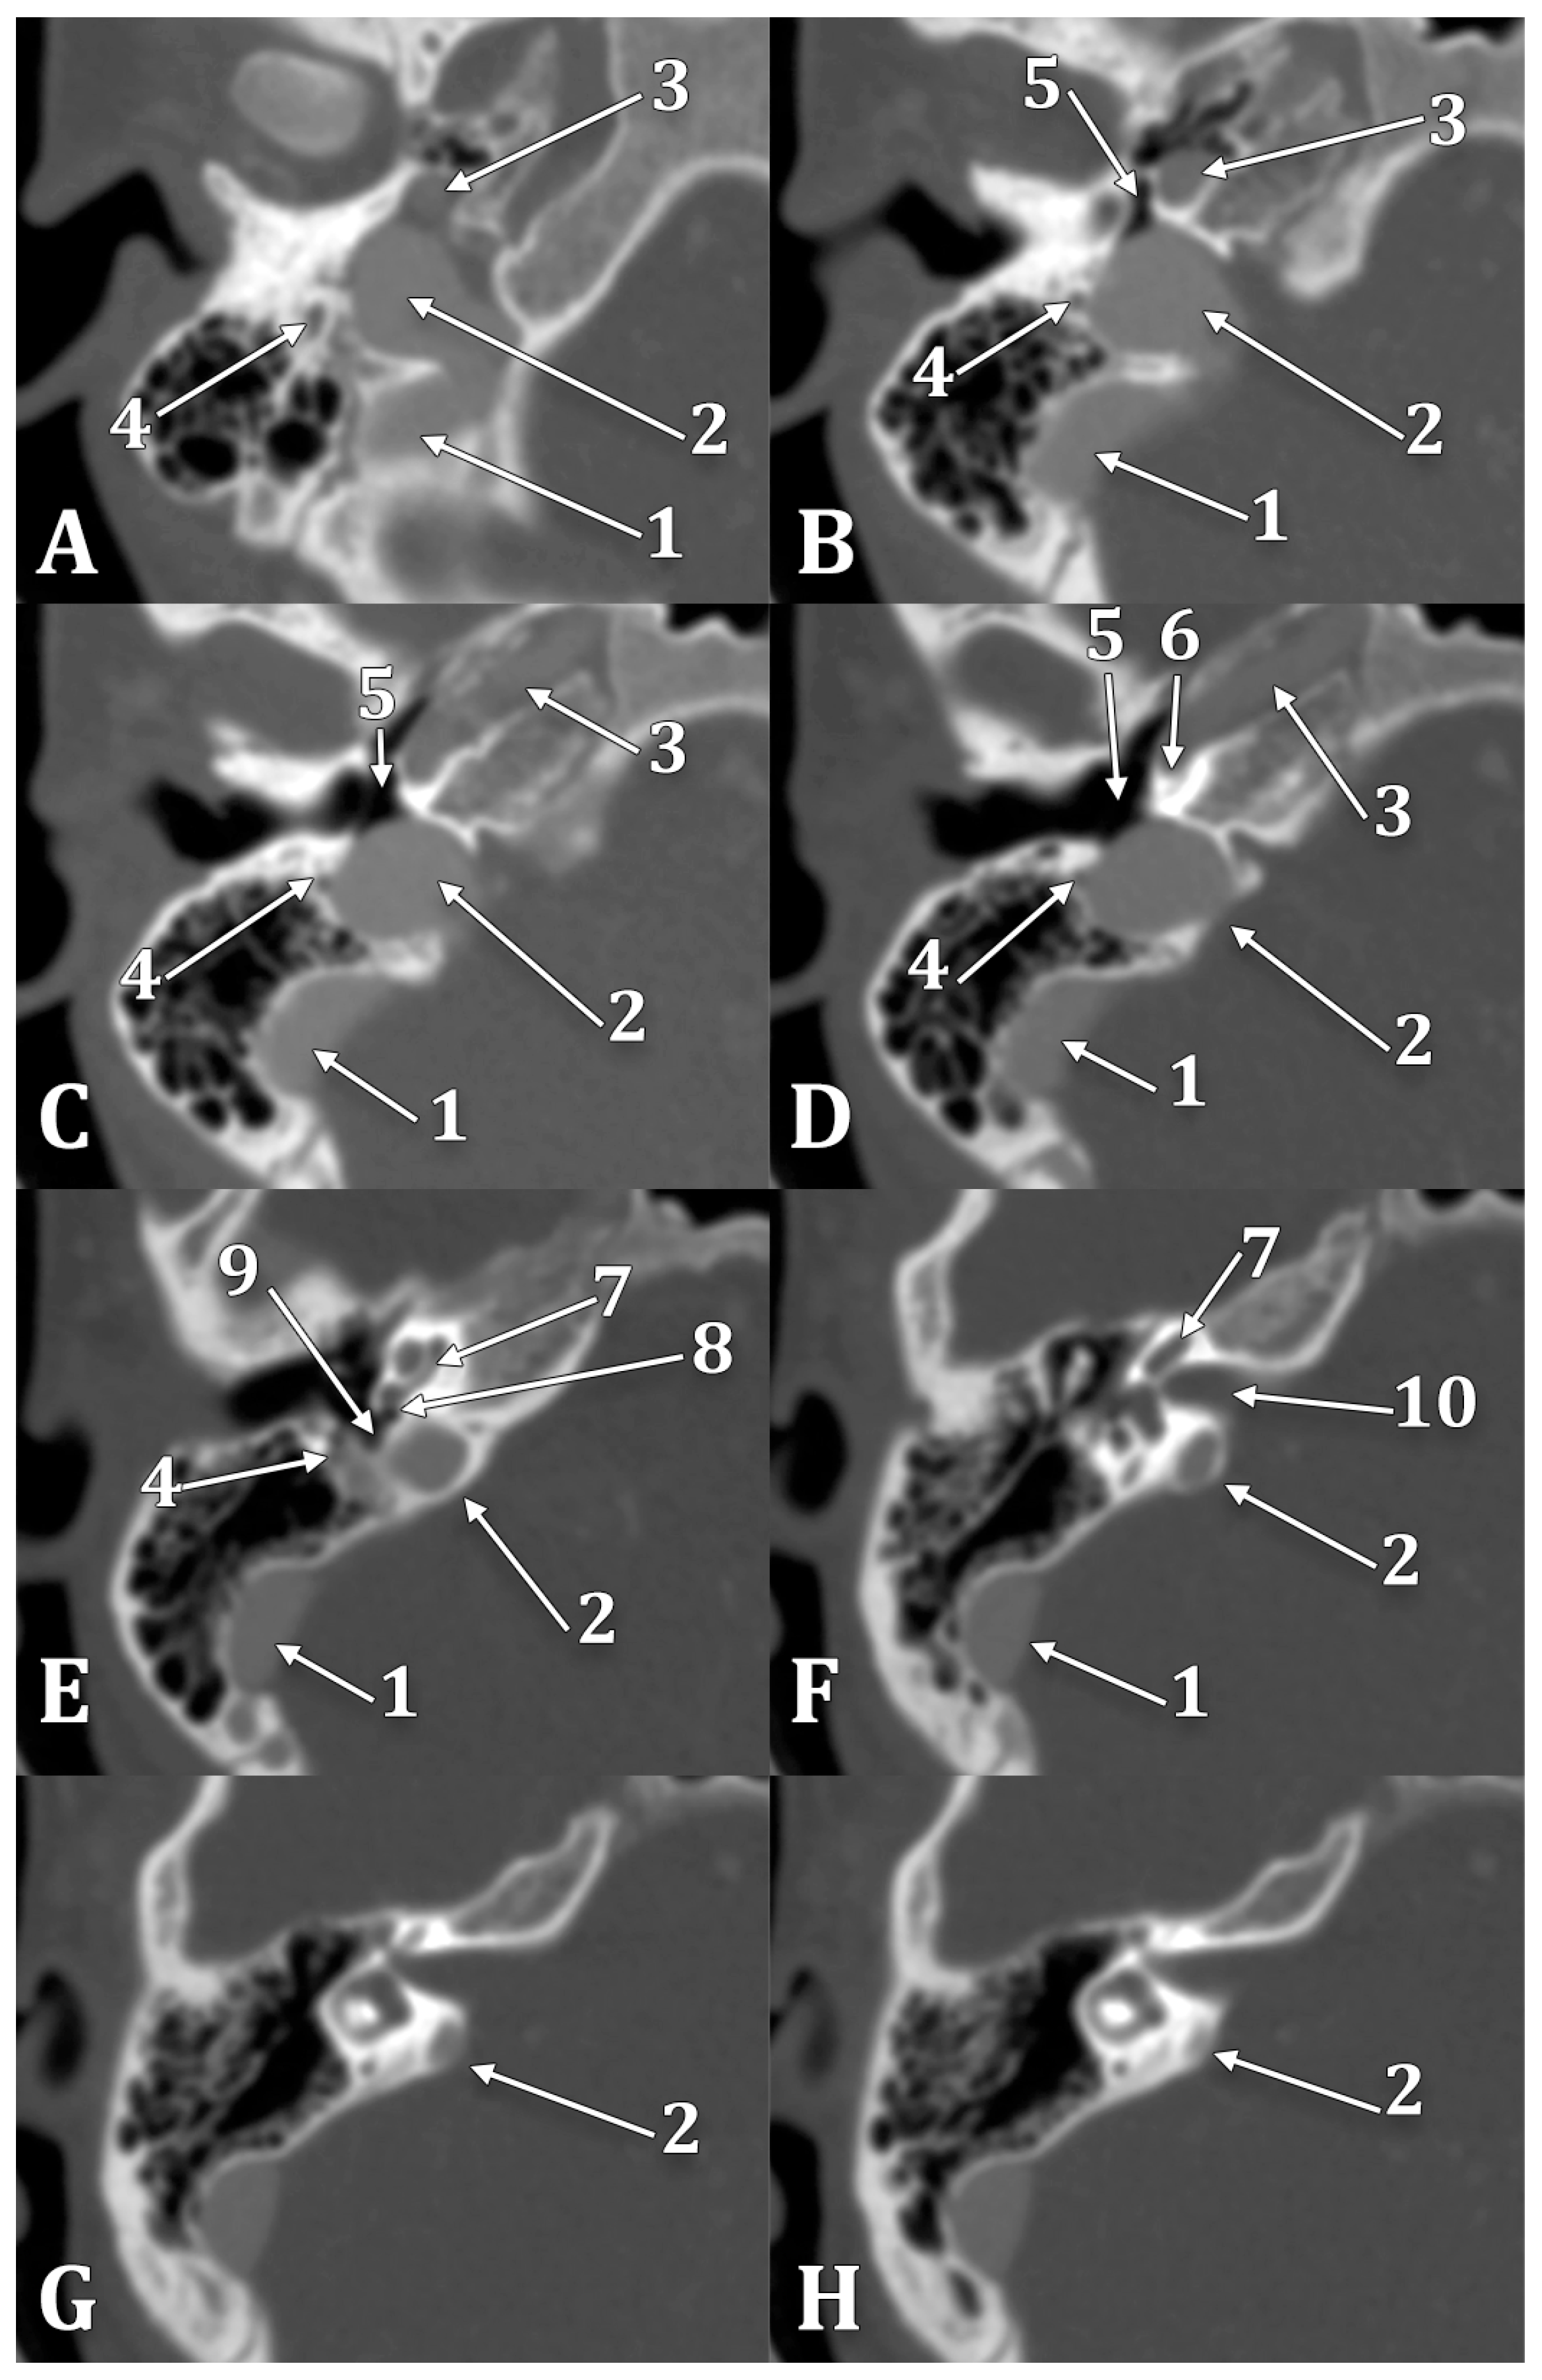

- Hourani, R.; Carey, J.; Yousem, D.M. Dehiscence of the jugular bulb and vestibular aqueduct: Findings on 200 consecutive temporal bone computed tomography scans. J. Comput. Assist. Tomogr. 2005, 29, 657–662. [Google Scholar] [CrossRef] [PubMed]

- Koesling, S.; Kunkel, P.; Schul, T. Vascular anomalies, sutures and small canals of the temporal bone on axial CT. Eur. J. Radiol. 2005, 54, 335–343. [Google Scholar] [CrossRef]

- Roche, P.H.; Moriyama, T.; Thomassin, J.M.; Pellet, W. High jugular bulb in the translabyrinthine approach to the cerebellopontine angle: Anatomical considerations and surgical management. Acta Neurochir. 2006, 148, 415–420. [Google Scholar] [CrossRef]

- Overton, S.B.; Ritter, F.N. A high placed jugular bulb in the middle ear: A clinical and temporal bone study. Laryngoscope 1973, 83, 1986–1991. [Google Scholar] [CrossRef]

- Inal, M.; Muluk, N.B.; Dag, E.; Arikan, O.K.; Kara, S.A. The Pitfalls and Important Distances in Temporal Bone HRCT of the Subjects with High Jugular Bulbs—Preliminary Report. Adv. Clin. Exp. Med. 2015, 24, 315–324. [Google Scholar] [CrossRef]